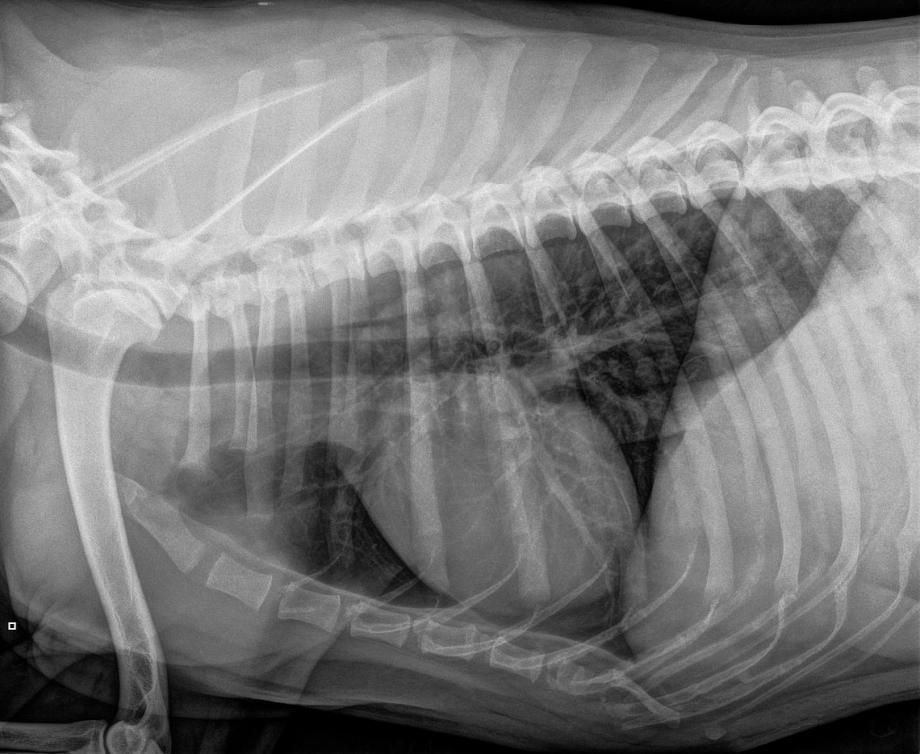

m Auftrag der Hilfsorganisation waren Bruströntgen angefertigt worden - auf den Bildern sind keine offensichtliche Veränderungen am Herzen zu sehen, wie sie bei unbehandeltem Herzwurmbefall auftreten könnten. Der Laborbericht eines Schweizer Grosslabors (Labor A) zeigt aber, dass im Blut Dirofilaria-Antigen gefunden wurde - ein Hinweis auf einen Herzwurmbefall.